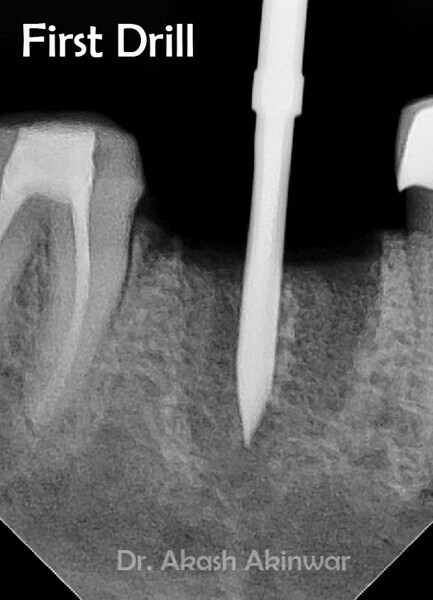

Flapless Single Implant Placement with Screw Retained PFM Prosthesis: Dr Akash Akinwar